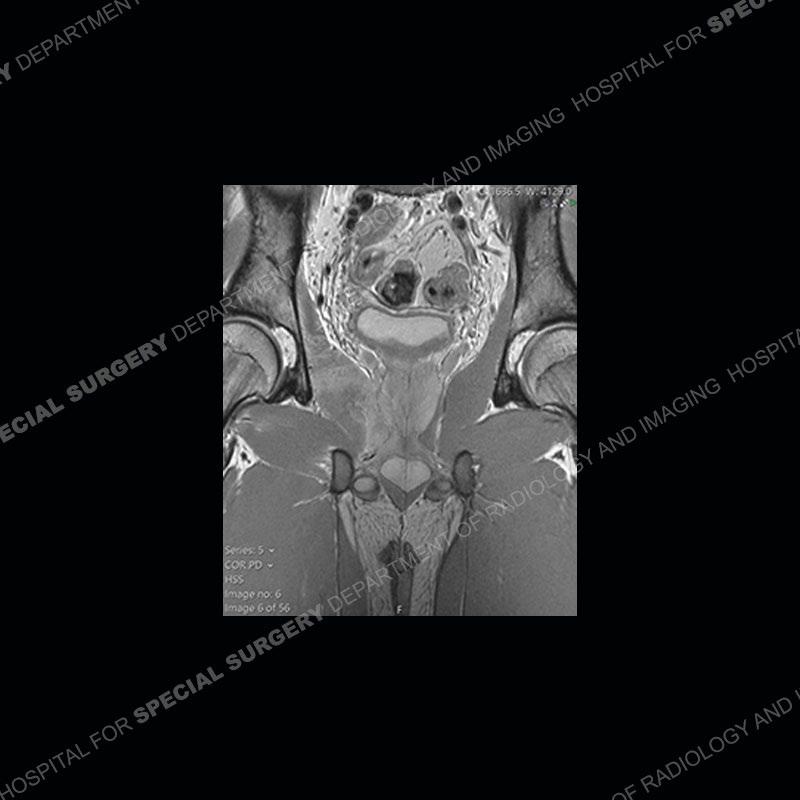

Radiographs did not demonstrate any clear abnormality. The MRI shows markedly abnormal signal of the right superior pubic ramus and abnormal signal/”mass” extending into the adjacent soft tissue. The inferior articular surface of the ramus showed what was thought to be bony destruction. CT examination shows a destructive process of the right superior pubic ramus.

Subsequent MRI in a very short time interval shows markedly increased abnormality of the ramus and increased edema and “mass” of the soft tissue. Post contrast imaging shows multiple, rim enhancing collections of the soft tissue and similar albeit less conspicuous enhancing collection of the ramus.

Diagnosis: Osteomyelitis and Soft Tissue Abscess

The repeat MRI, with the marked degree of increased abnormality of the bone and soft tissue shifted the diagnosis to a high degree towards infection. Even the most aggressive of neoplasms would not have that the degree of change in a 3-day time span. The CT study was shown before the repeat MRI but actually occurred just after the repeat MRI. It helped confirm the destructive process of the ramus and particularly the abnormal architecture along the inferior margin. The patient went on to have a CT guided aspiration of one of the soft tissue collections with 4cc of purulent fluid obtained. A surgical irrigation and debridement of the bone and soft tissue was performed. A PICC line was placed and the patient is currently undergoing IV antibiotic treatment with a possible repeat irrigation and debridement.